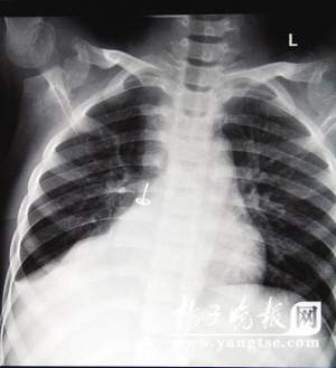

从片子上,图钉在孩子右肺里“潜伏”得很深,卡在右下叶支气管。南京市儿童医院耳鼻喉科周艾医生表示,由于图钉堵住了孩子支气管的通道,导致右肺叶不扩张,肺部已经发生了实质性的改变,用扩张来进行氧气交换的肺泡都已经“瘪”下去了,所以孩子的肺部功能非常弱。从片子上看,孩子的右肺已经严重“萎缩”,比左肺小了一大圈。